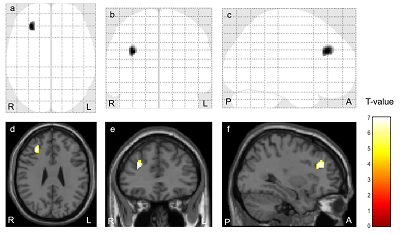

研究グループでは、日本医療研究開発機構(AMED)の研究班「筋痛性脳脊髄炎/慢性疲労症候群に対する診療・研究ネットワークの構築(研究代表者:山村隆)」において、ME/CFS診療を行っている内科医との連携を構築し、神経研究所免疫研究部と病院放射線診療部が連携して免疫学的解析・脳画像解析を進めている。先行研究において、MRIの最新の拡散イメージング手法である拡散尖度画像(Diffusional Kurtosis Imaging:DKI)、拡散イメージングの新たな画像処理手法である神経突起イメージング(Neurite Orientation Dispersionand Density Imaging:NODDI)を用いて右上縦束の異常を検出し、ME/CFSの症状である脳内処理作業やワーキングメモリの機能低下の原因である可能性を示している。そこで、研究グループは、ME/CFS患者の脳内構造ネットワーク異常と抗自律神経受容体受容体抗体価との相関を調べ、抗自律神経受容体受容体抗体がME/CFS患者の脳にどのような影響を与えているのかを調べた。

調査は、2015年10月~2019年10月までの間にNCNP病院を受診し、ME/CFSの国際的な診断基準を満たし、3テスラMRI撮像と自律神経受容体に対する自己抗体測定を実施した89人(男性13人、女性76人;平均年齢37.3歳、右利き手)を対象とした。測定した血清抗体は、抗β1アドレナリン受容体抗体、抗β2アドレナリン受容体抗体、抗M3アセチルコリン受容体抗体、抗M4アセチルコリン受容体抗体で、血液採取とMRI撮像は30日以内に実施。ネットワーク解析では、局所脳のネットワーク指標である次数、クラスタリング係数、媒介中心性、特徴的経路長とともに、全体脳のネットワーク指標であるスモールワールド性を解析した。その結果、抗β1アドレナリン受容体自己抗体価と右背外側前頭前野の媒介中心性との間に正の相関、抗β2アドレナリン受容体自己抗体価と右中心前回の特徴的経路長との間に負の相関を認めた。

背外側前頭前野は、注意力やワーキングメモリに関与する他、痛みの調整も担っている。つまり、抗β1アドレナリン受容体自己抗体は右背外側前頭前野に微小な構造変化を引き起こし、注意力やワーキングメモリの低下、痛みの調整の異常をきたしている可能がある。背外側前頭前野は、上縦束が投射する部位であり、先行研究で示された右上縦束の異常に密接に関連していると考えられた。

また、中心前回は運動を司る部位として有名だが、慢性疼痛患者では中心前回が活性化し、前頭前野、中心後回、視床を介して痛みの調整を行っていると考えられている。特徴的経路長の減少は、持続的な痛みによる中心前回の活性化を反映していると考えられ、その原因として抗β2アドレナリン受容体自己抗体の存在が考えられた。